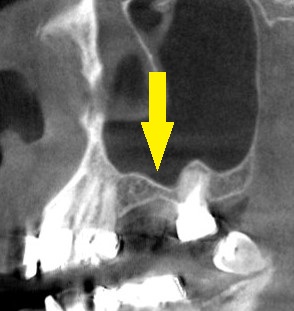

レントゲン、CTを撮影してみると、上顎の臼歯部ではよくあることですが、骨がやや薄く骨造成なしでインプラント埋入は困難でした。

下の写真2段目が術前のCT、やや骨が薄いのが分かります。